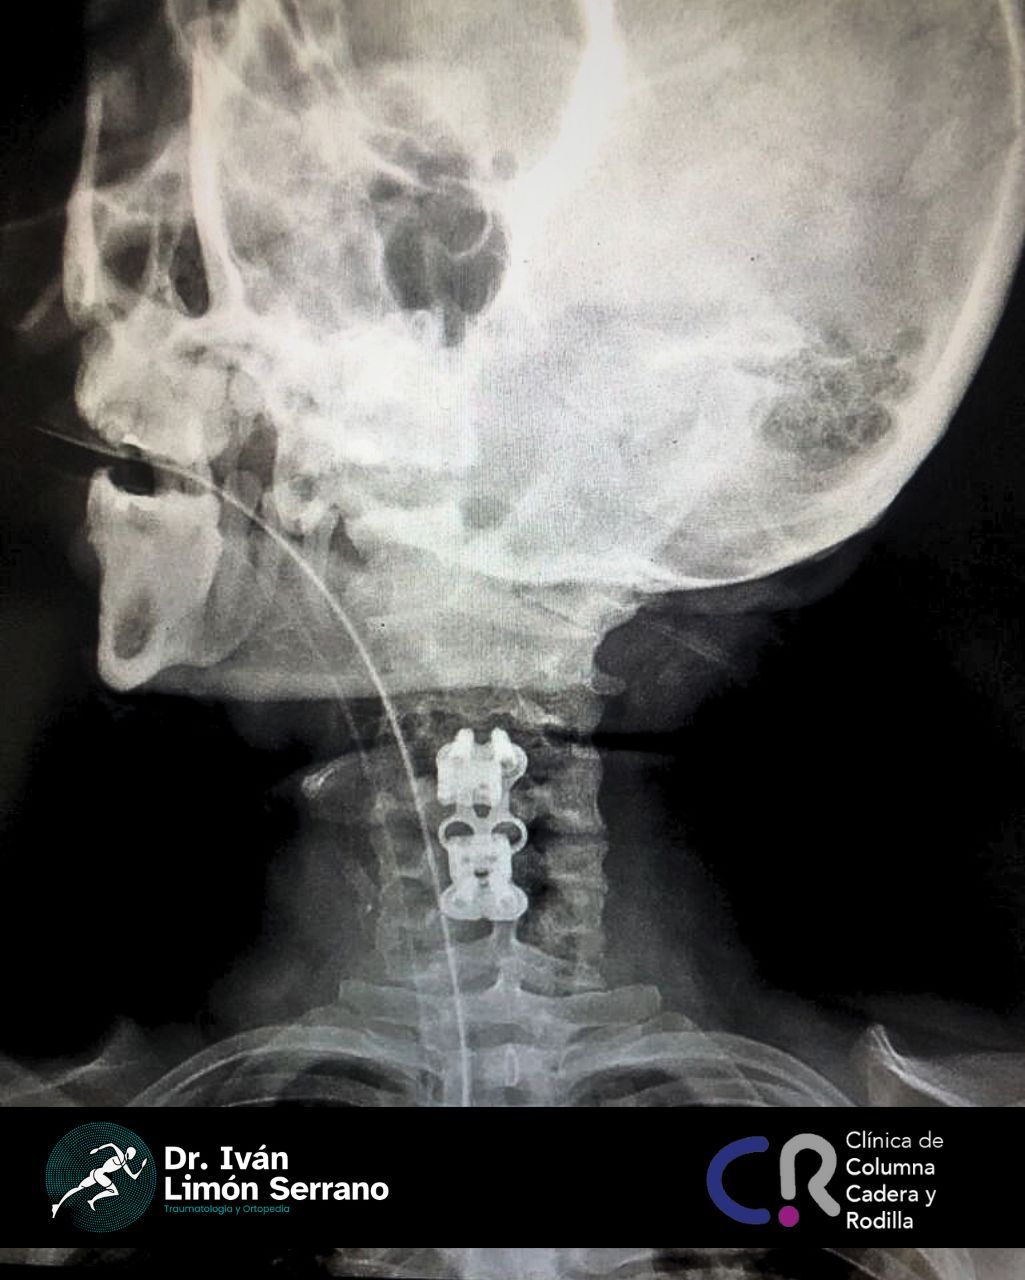

• Cirugía de columna

• Cirugía columna